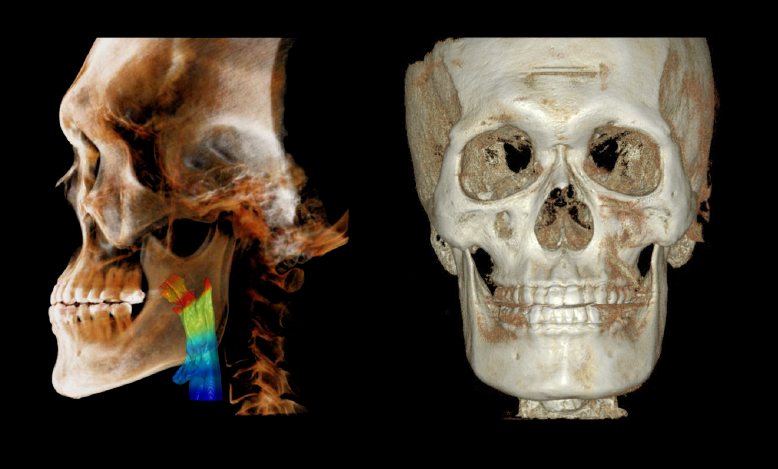

ODONTOLOGÍA IMPULSADA POR EL ROSTRO

Escáner Facial 3D + CBCT + Escáner Intraoral

Libere el potencial de las SOLUCIONES BASADAS EN EL ROSTRO: obtenga resultados de tratamientos personalizados y estéticamente agradables, al capturar el espectro completo de la anatomía facial y dental. La avanzada tecnología de RAYSCAN S garantiza imágenes completas de los huesos faciales y dentales, todo mientras minimiza la exposición a la

radiación. Con nuestros escáneres facial e intraoral 3D, la planificación específica para cada paciente se vuelve una herramienta transformadora e indispensable, preparada para mejorar e inspirar vidas.

Un escaneo con todos los detalles

RAYSCAN S puede capturar una región completa de la anatomía con facilidad y precisión. Su extraordinaria capacidad para capturar toda la anatomía en un sólo escaneo es realmente impresionante.